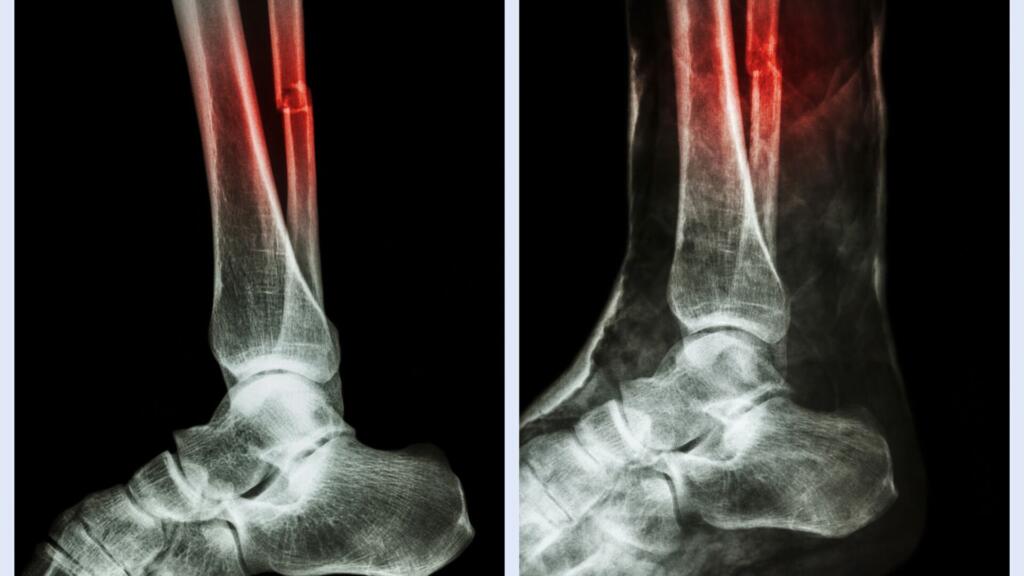

El accidente tuvo lugar en Las Rozas, donde la futbolista sufrió una torcedura tras un apoyo incorrecto en una jugada fortuita. Las primeras pruebas médicas confirmaron la fractura y, tras una revisión más exhaustiva en Barcelona, se decidió intervenir quirúrgicamente. La operación fue realizada por el doctor Antoni Dalmau en el Hospital de Barcelona, bajo la supervisión de los Servicios Médicos del club.